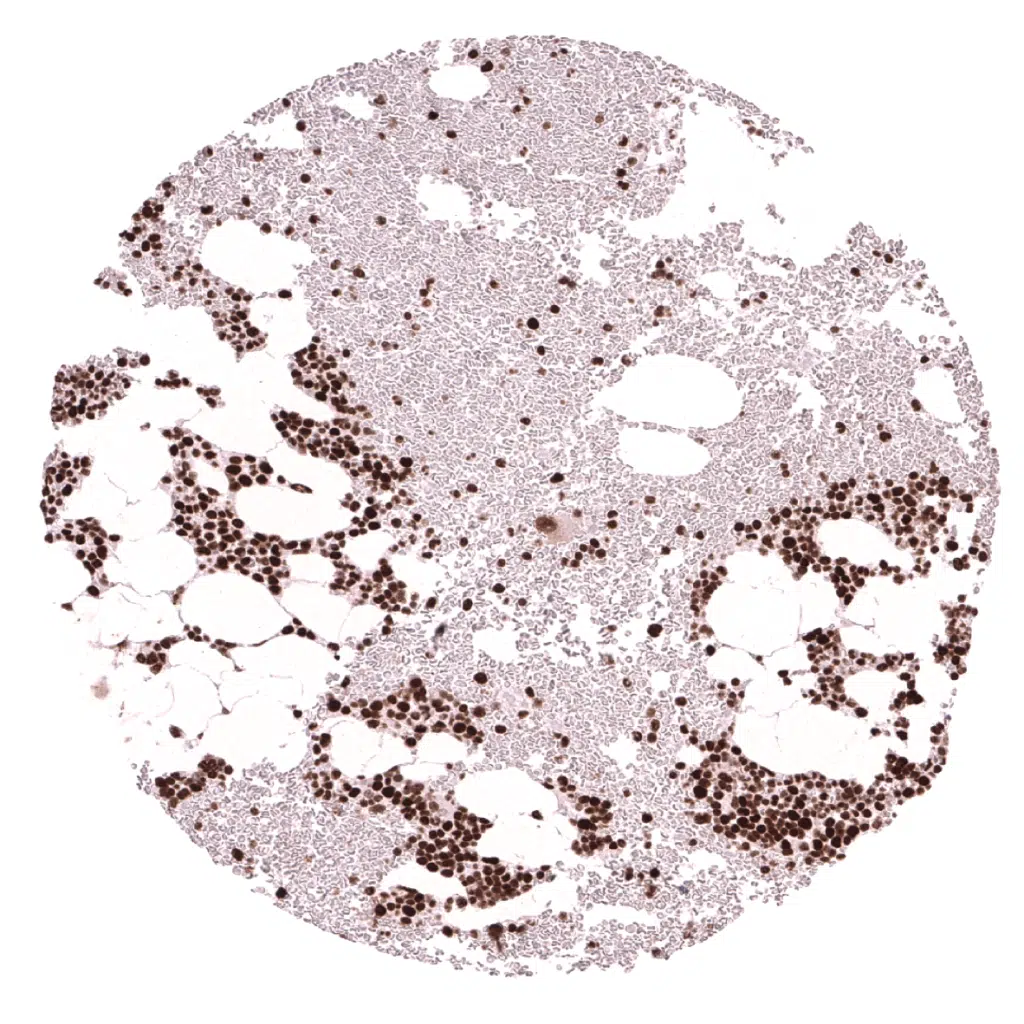

Spleen